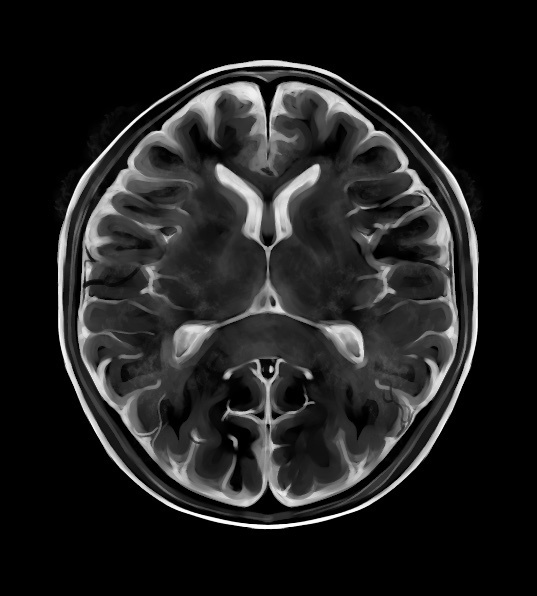

「脳MRI 1(正常解剖)」高橋 昭喜定価: ¥ 9800脳MRI(代謝、脱髄、変性、外傷他)定価12000円名前跡を消しています#高橋昭喜 #高橋_昭喜 #本 #自然/医療・薬学・健康 #放射線科 #脳 #画像診断

脳MRI 2 .3セット - 健康・医学

脳MRI 2 .3セット - 健康・医学

よくわかる脳MRI 第2版 (画像診断別冊KEY BOOKシリーズ)

よくわかる脳MRI 第2版 (画像診断別冊KEY BOOKシリーズ)